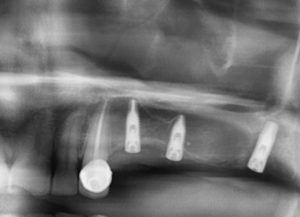

1. Evaluación y planificación: Se realiza un estudio detallado con radiografías y escáneres 3D para determinar la viabilidad del tratamiento.

2. Colocación del implante: Bajo anestesia local, el implante se inserta en el hueso maxilar o mandibular.

3. Cicatrización y osteointegración: Durante unos meses, el implante se fusiona con el hueso, asegurando su estabilidad.

Es importante contar con suficiente cantidad de hueso maxilar para soportar el implante. Si este no es el caso, existen procedimientos complementarios como la regeneración ósea guiada o el injerto de hueso.